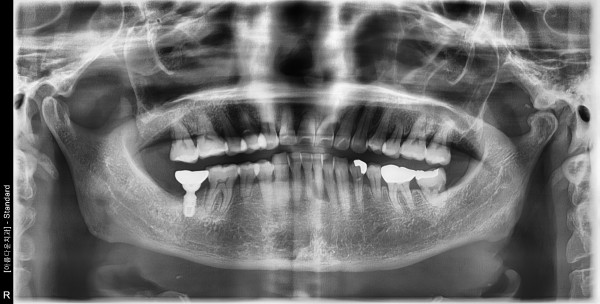

61세 여/ 하악 구치부 발치, 치조골 이식술 후 임플란트 식립